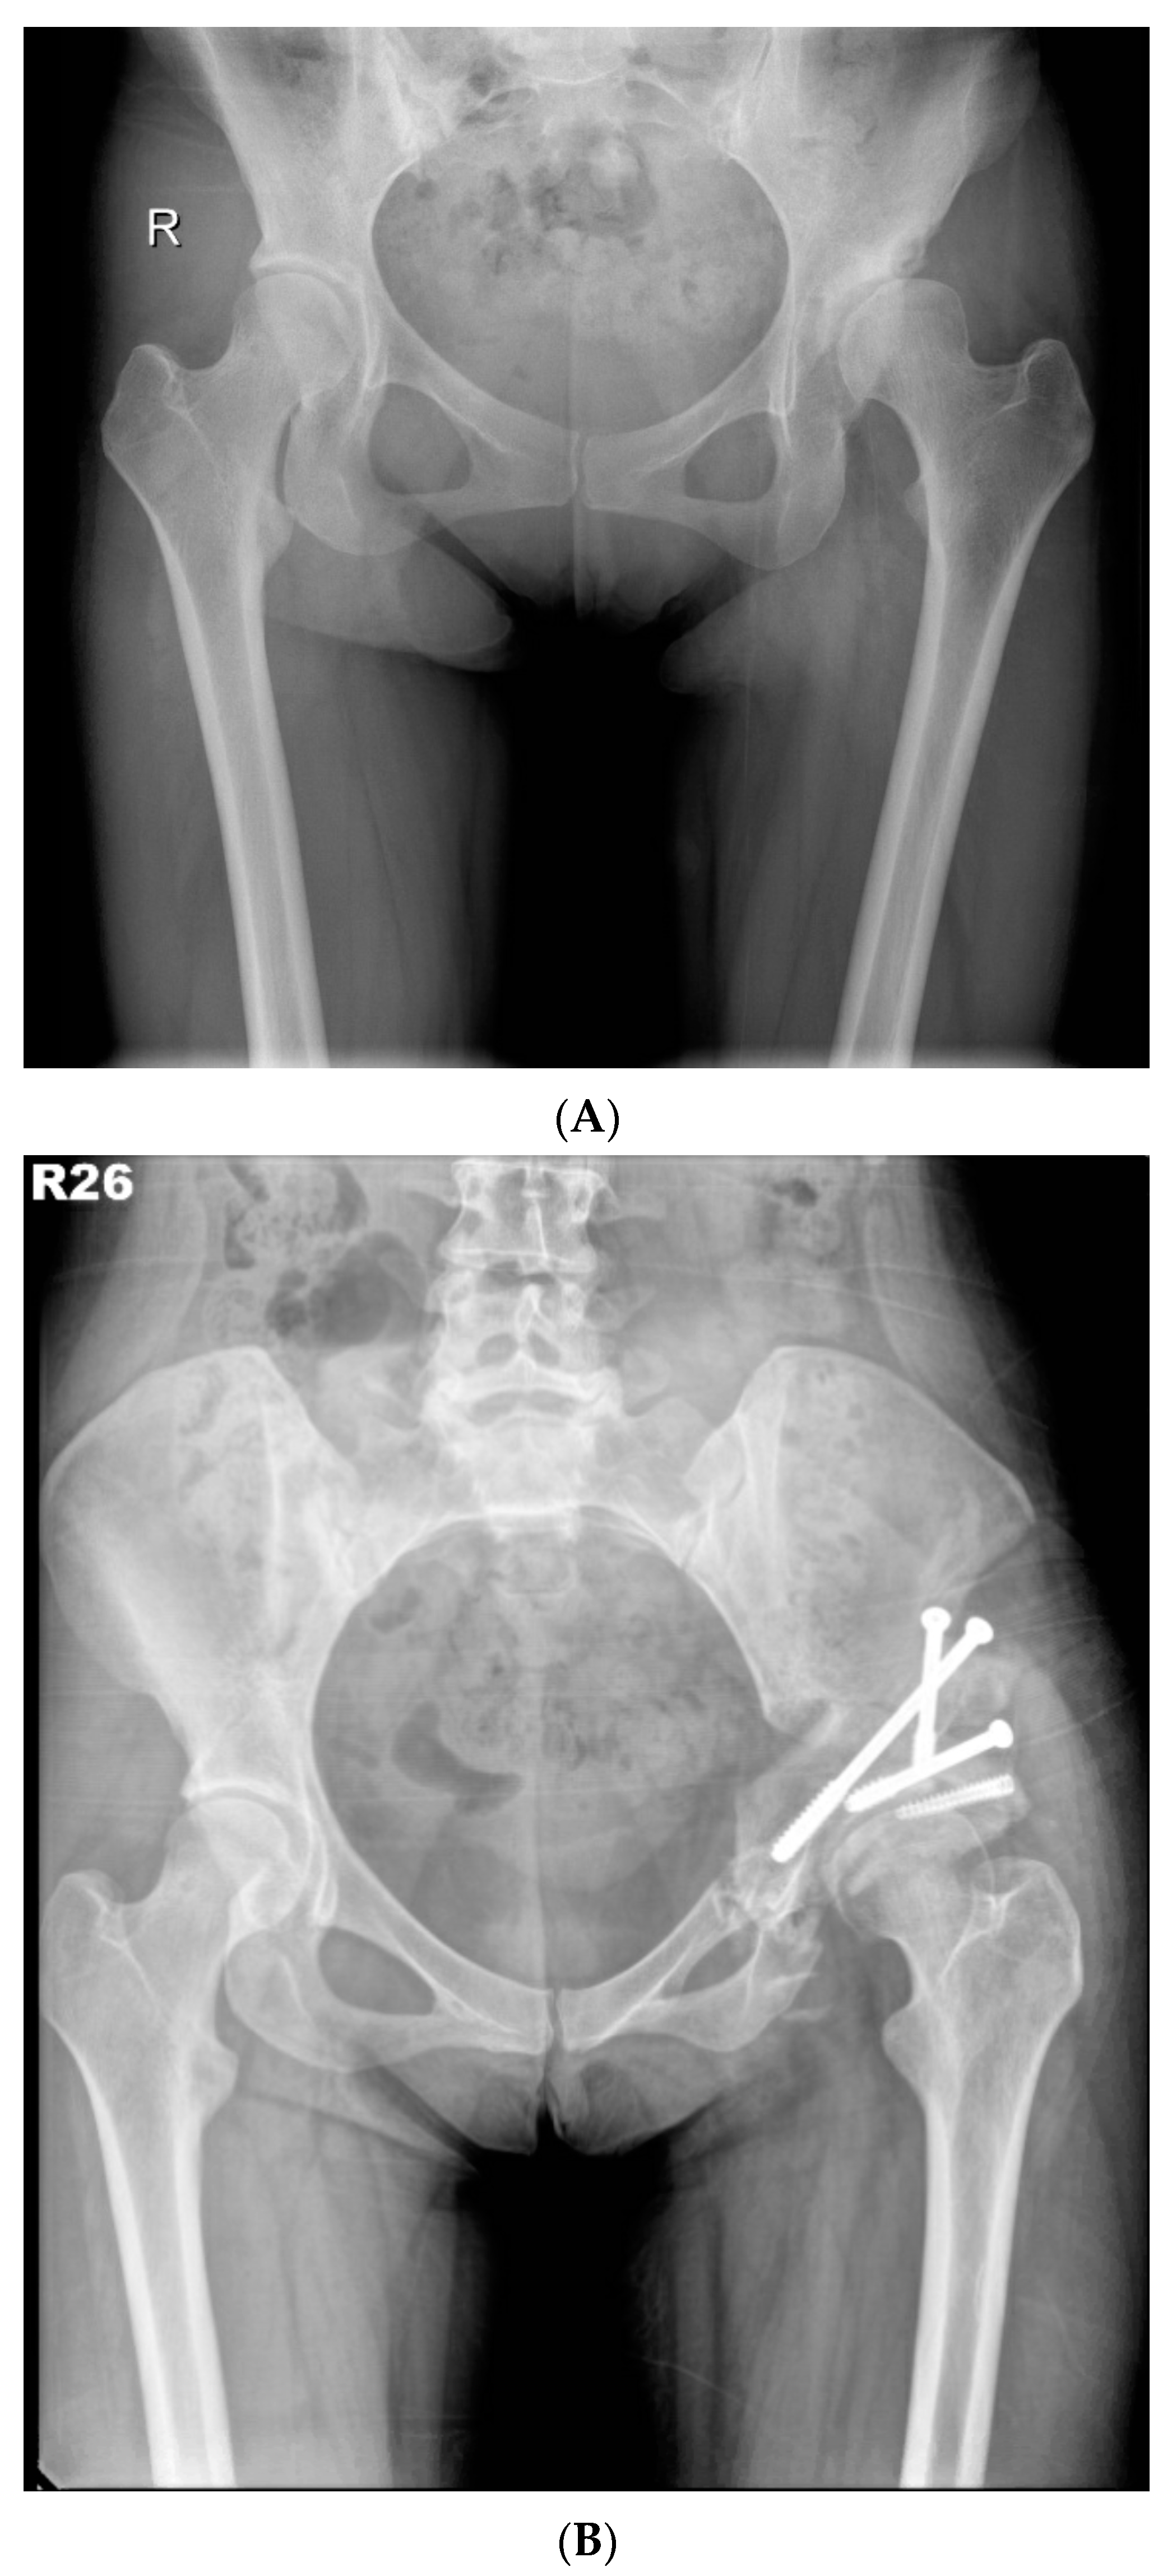

In 2012, we proposed a modified approach for triple innominate osteotomy [8] with the advantage of more favourable femoral-head medialisation and coverage when compared with the traditional approach. In this study, the modified approach was implemented as follows (Figure 2A,B).

Figure 2. (A) Preoperative anteroposterior standing radiograph of a 26-year-old woman who underwent MTI osteotomy for symptomatic left hip dysplasia. (B) Postoperative anteroposterior standing radiograph showed good coverage of the femoral head.